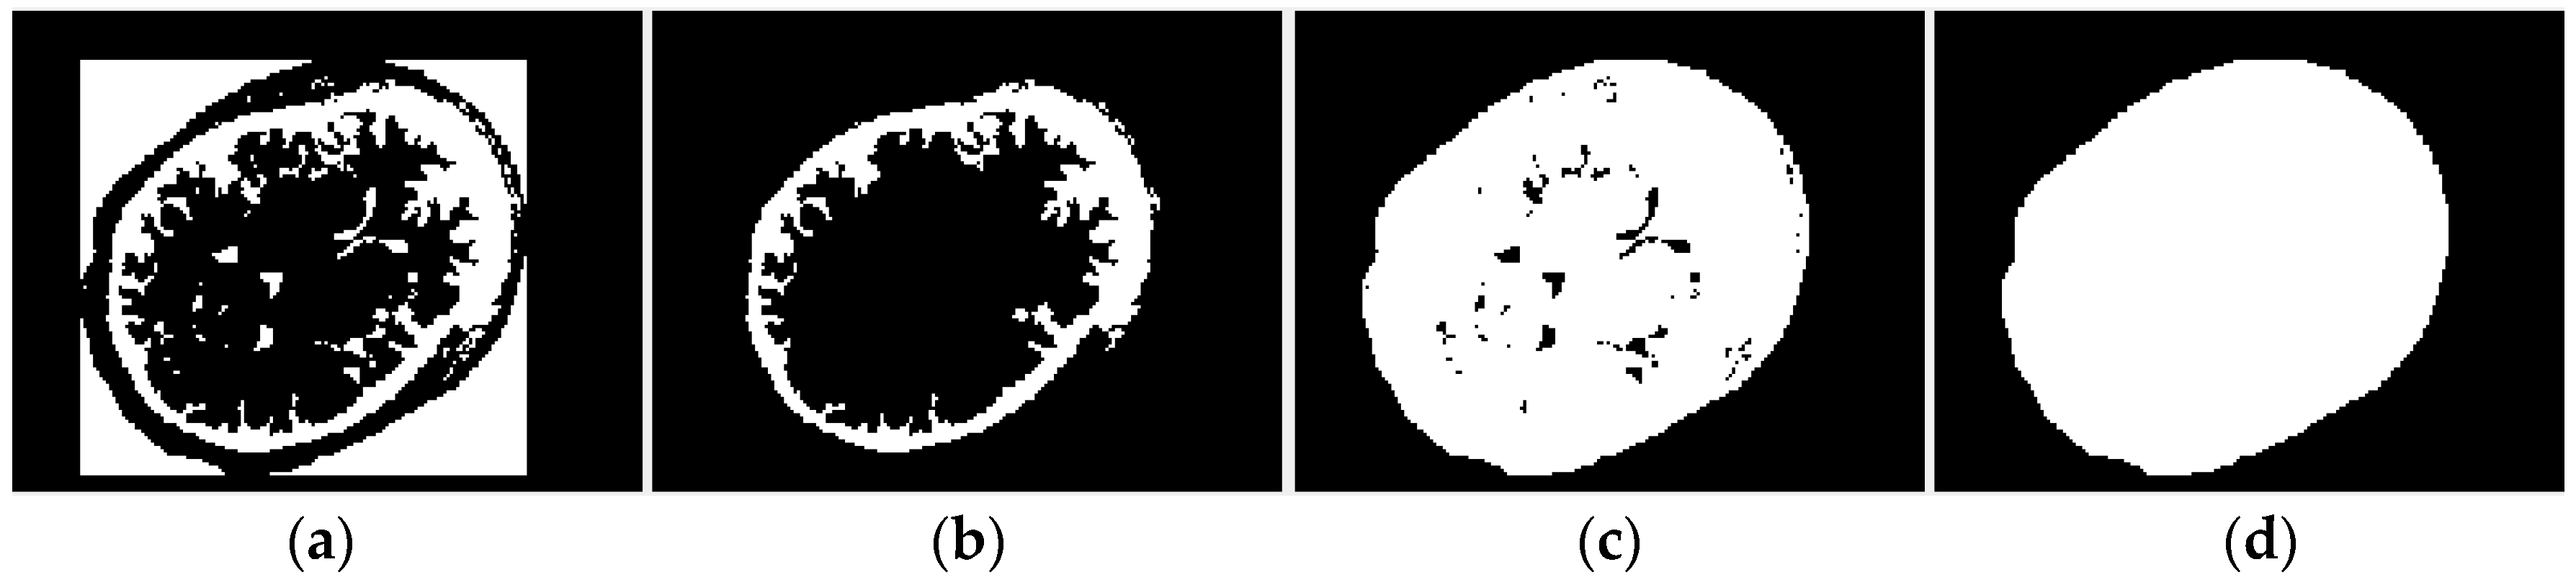

2.2.1. Region of Interest Extraction